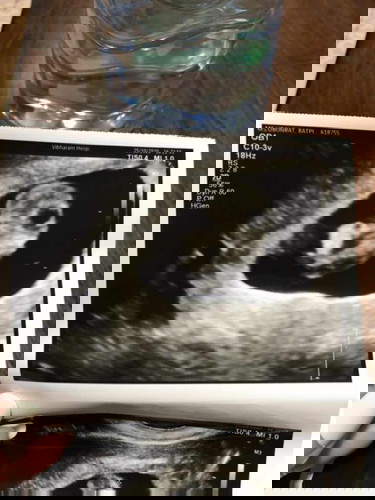

ยุติการตั้งครรภ์ 9 สัปดาห์ ซาวด์แล้วไม่พบหัวใจ

ท้องแรกค่ะ วันนี้อายุครรภ์ 9 สัปดาห์ คุณหมอนัดตรวจอัพเดทเพื่อที่จะฝากครรภ์ แต่พอซาวด์ดูไม่พบหัวใจไม่มีชีพจร คุณหมอได้แจ้งว่าต้องยุติการตั้งครรภ์ และนัดขูดมดลูก รบกวนสอบถามคุณแม่ท่านไหนเคยเจอแบบนี้บ้าง และรอนานไหมกว่าจะท้องได้อีกครั้ง ตั้งใจอยากมีลูกมากค่ะ วันนี้เป็นวันที่เสียใจที่สุดเลยค่ะ